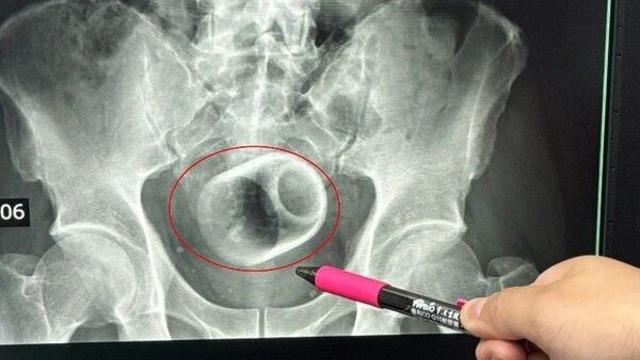

항문 속 컵 3일간 참은 남성…부끄러워 숨기다 장 괴사